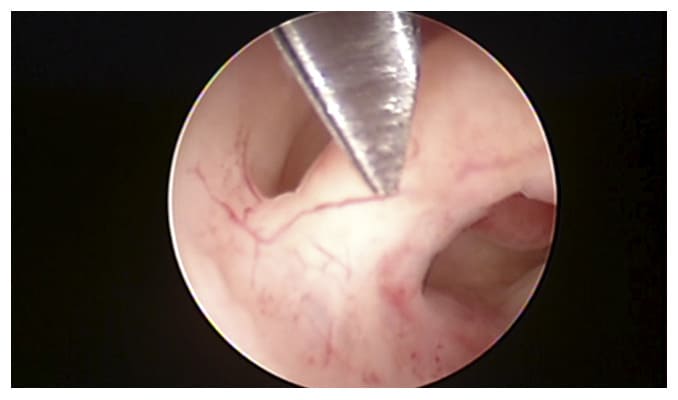

El tratamiento es por histeroscopia ( una cirugía ambulatoria donde se introduce una cámara dentro del útero para extraer el pólipo)